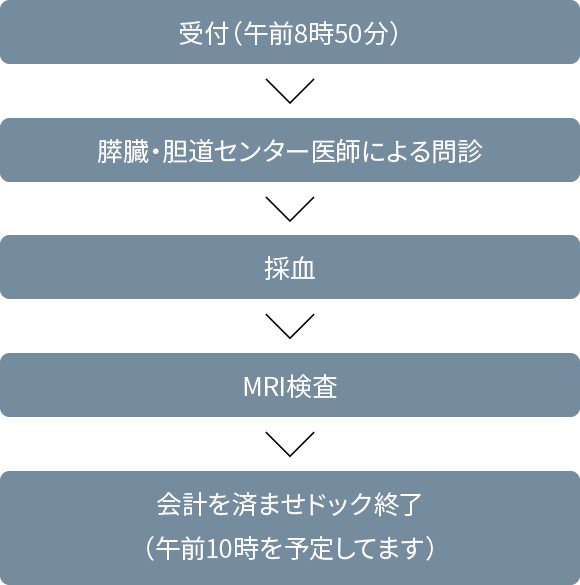

問診、採血、MRI、により膵がん、胆道がんの可能性のある方をスクリーニングします。

17,600円(税込)

(糸魚川市民の45歳以上の方には、糸魚川市より半額の補助が出ます。申し込み時にお申し出ください。)

(1日1名の予約枠です)